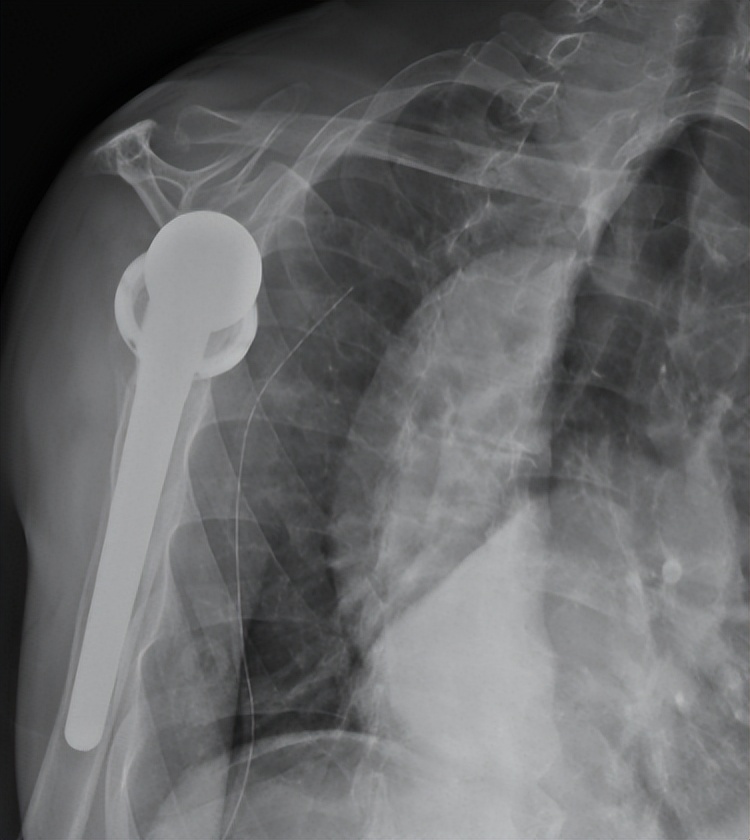

术后X线

在麻醉手术科医护人员的配合下,创伤中心成功实施了“反置式人工全肩关节置换术”,采用人工假体替代受损的肱骨头和关节盂。术后陈大爷恢复顺利,在科室康复医师的帮助下进行康复锻炼,功能获得明显改善。

反式人工全肩关节置换术是指肩关节假体的球形关节面置于肩胛骨关节盂侧,而盂杯放置于肱骨近端的半限制性人工全肩关节。反肩置换术是肩关节复杂毁损性病变的拯救术式,是利用三角肌来替代肩袖的动能,但由于对适应证限制,手术难度等原因,在国内开展较少。反肩置换主要适用于难以复位固定的老年肱骨近端骨折、陈旧性肱骨近端骨折不愈合或合并骨缺损、骨折内固定失败翻修、难以修复的巨大肩袖撕裂等。作为山东省医师协会骨科分会主委单位、山东省医师协会肩肘外科专业委员会主委单位,创伤中心多年致力于肩肘复杂创伤的研究,该疑难手术的顺利实施,体现了我院处理复杂肩肘创伤病例的领先能力。